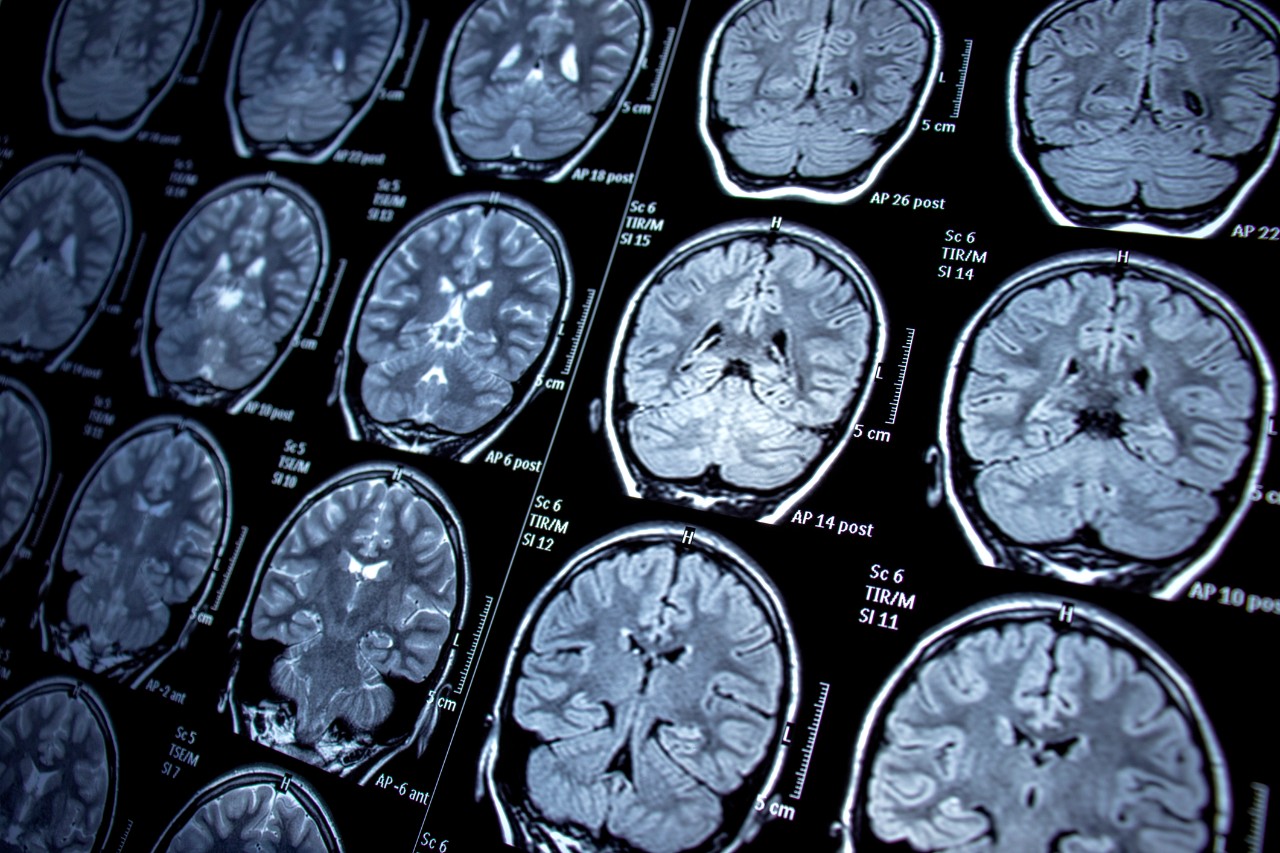

Researchers at the University of Cincinnati and Dell Medical School at the University of Texas at Austin (Dell Med) are leading a study using state-of-the-art neuroimaging techniques and artificial intelligence to identify changes in the brains among children of adults living with bipolar disorder — a debilitating condition that interferes with daily life due to its dramatic mood, energy and activity level shifts.

The research leverages AI algorithms to discern variations in participants’ brains, combining imaging data with cognitive, clinical, early life adversity and psychosocial function measures. The result is a precise delineation of brain maturation for each person at risk of developing bipolar disorder.

The five-year longitudinal study uses functional magnetic resonance imaging to identify early signs that the brain is developing bipolar disorder. Participants ages 14-21 — a critical time when mania symptoms often develop — undergo annual brain scans to track changes in the brain. If they become depressed, suicidal or experience mania, the participants undergo additional brain scans to help researchers understand how the damage is unfolding.

Featured photo at top of brain scans. Photo/Nur Ceren Demir/iStock.